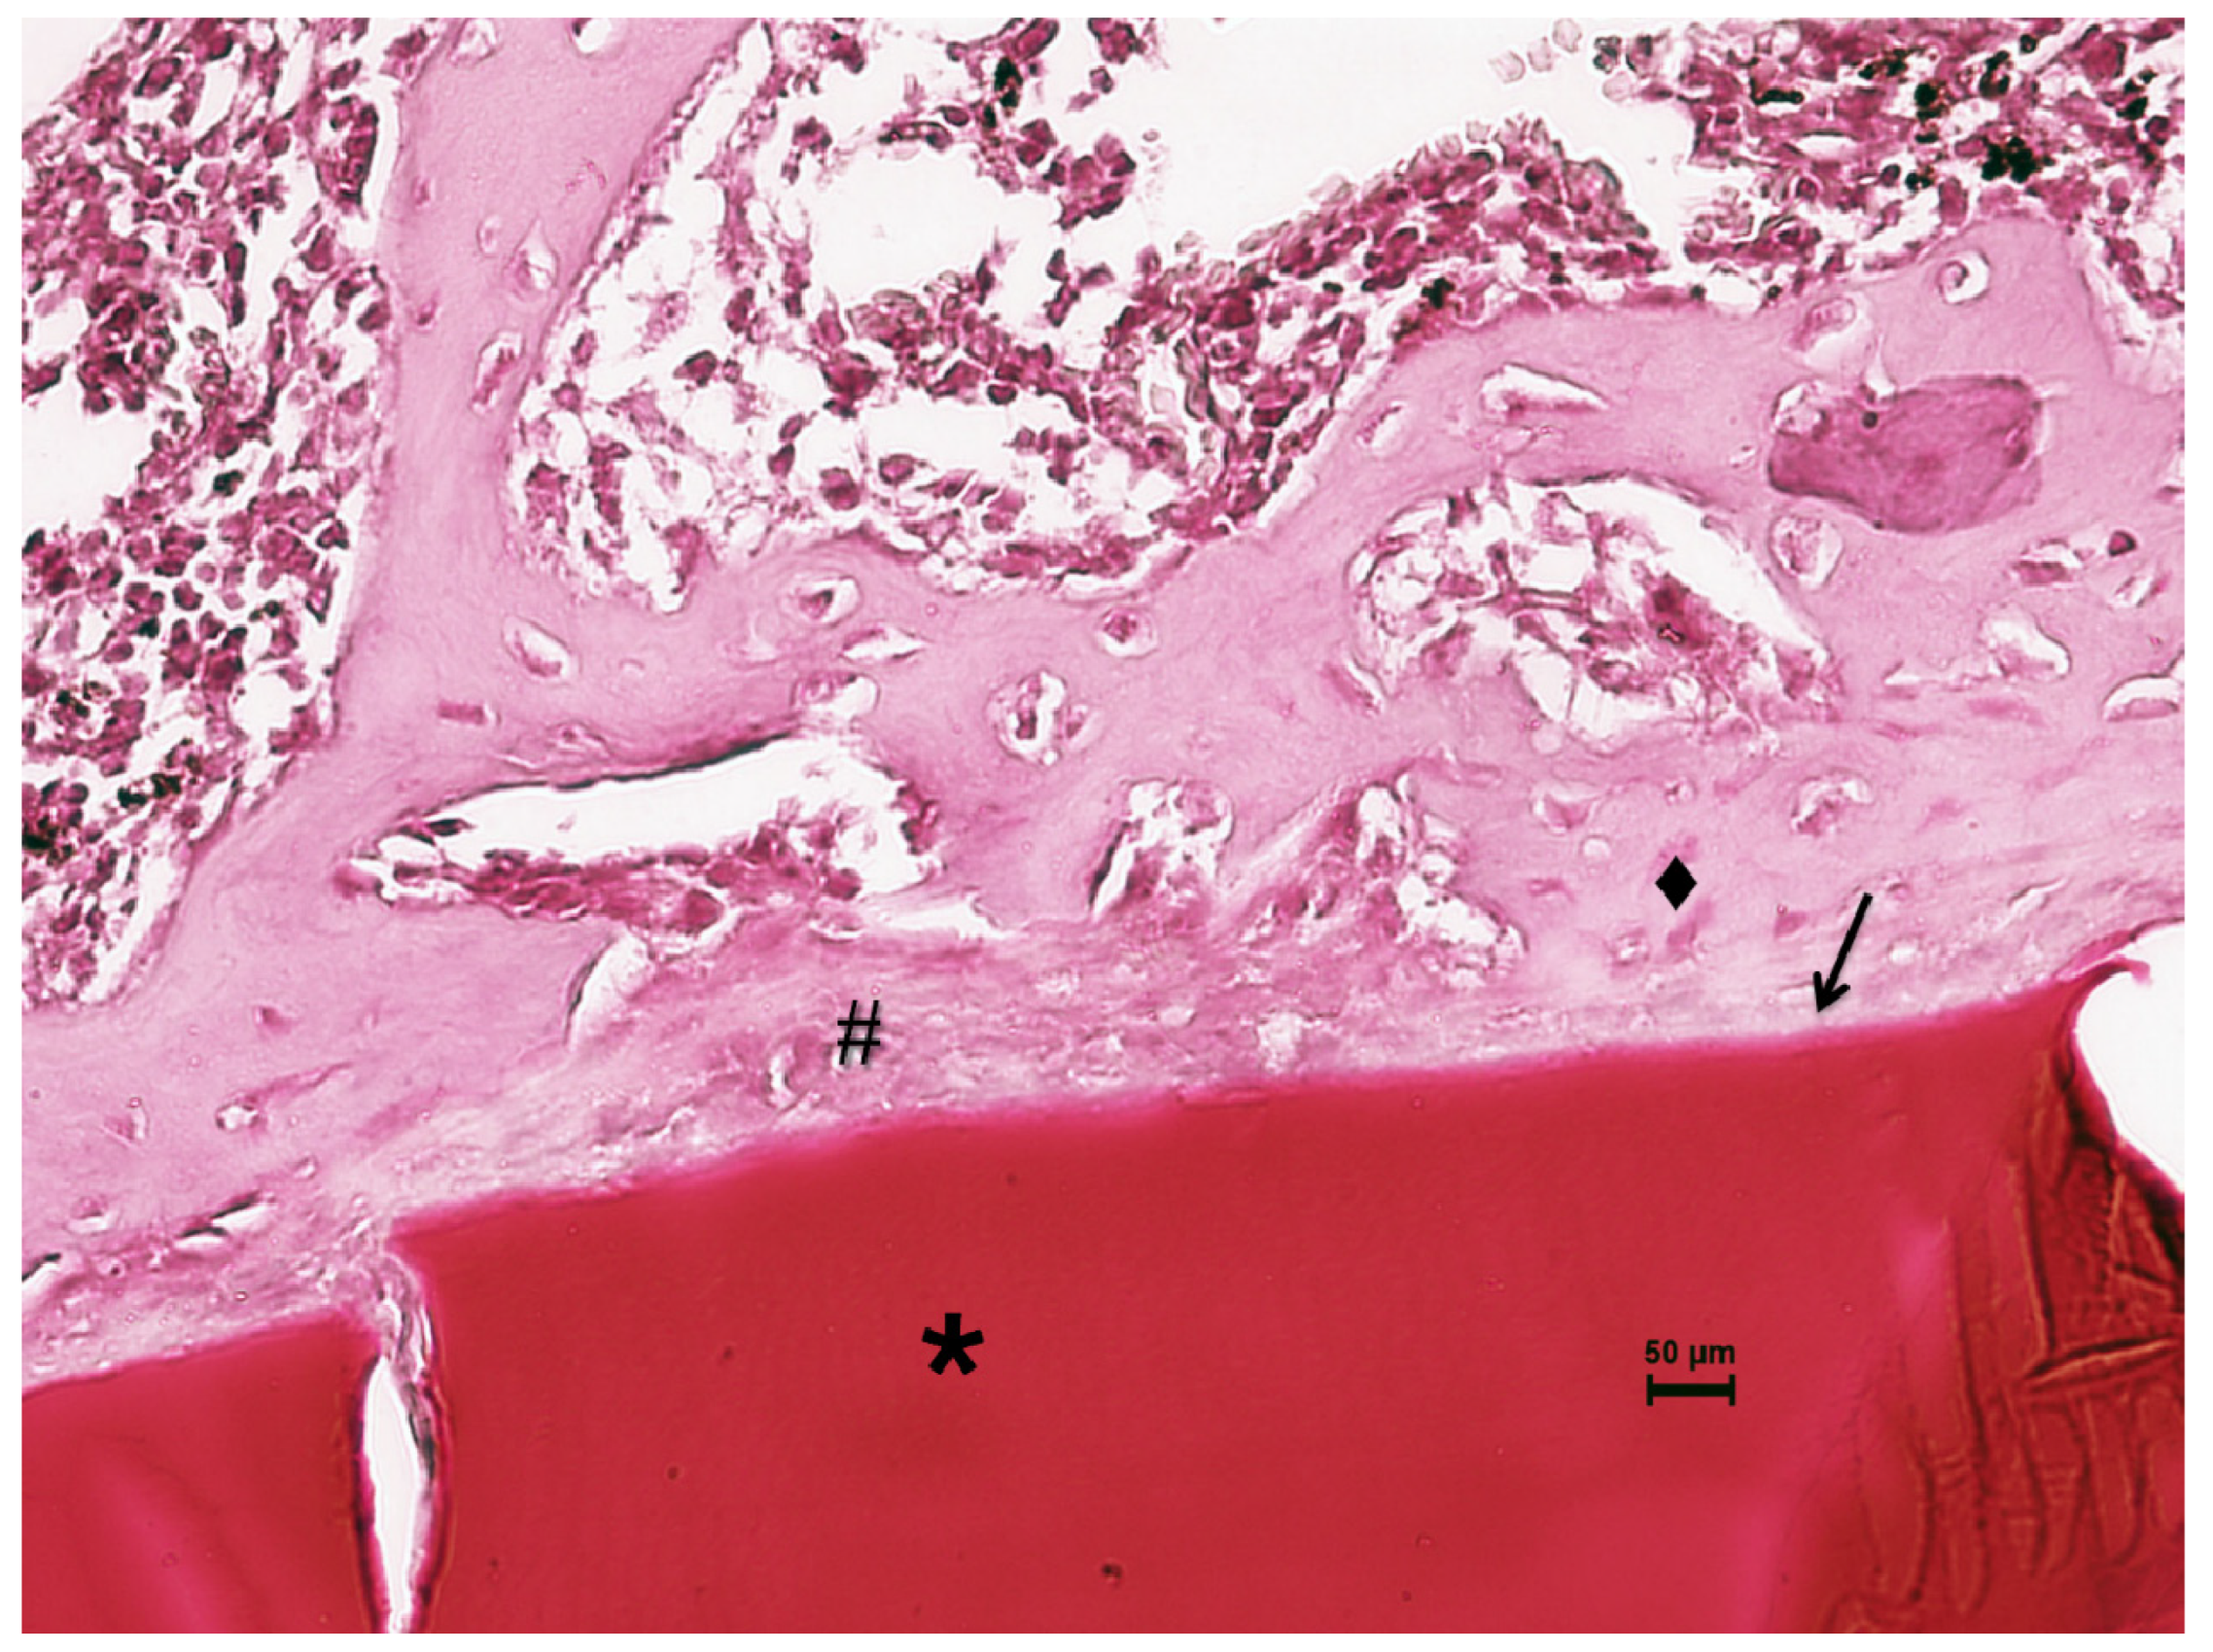

Histological Analysis